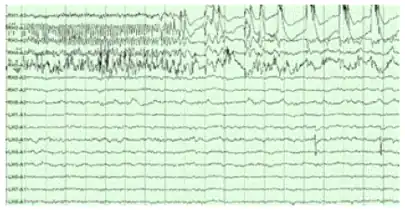

The hippocampus shows two major modes of activity, each associated with a distinct pattern of neural population activity and waves of electrical activity as measured by an electroencephalogram (EEG). These modes are named after the EEG patterns associated with them: theta and large irregular activity (LIA). The main characteristics described below are for the rat, which is the animal most extensively studied.[112]

The theta mode appears during states of active, alert behavior (especially locomotion), and also during REM sleep (dreaming).[113] In the theta mode, the EEG is dominated by large regular waves with a frequency range of 6 to 9 Hz, and the main groups of hippocampal neurons (pyramidal cells and granule cells) show sparse population activity, which means that in any short time interval, the great majority of cells are silent, while the small remaining fraction fire at relatively high rates, up to 50 spikes in one second for the most active of them.[114][115] An active cell typically stays active for half a second to a few seconds. As the rat behaves, the active cells fall silent and new cells become active, but the overall percentage of active cells remains more or less constant. In many situations, cell activity is determined largely by the spatial location of the animal,[116] but other behavioral variables also clearly influence it.

The LIA mode appears during slow-wave sleep (non-dreaming), and also during states of waking immobility such as resting or eating.[113] In the LIA mode, the EEG is dominated by sharp waves that are randomly timed large deflections of the EEG signal lasting for 25–50 milliseconds. Sharp waves are frequently generated in sets, with sets containing up to 5 or more individual sharp waves and lasting up to 500 ms. The spiking activity of neurons within the hippocampus is highly correlated with sharp wave activity. Most neurons decrease their firing rate between sharp waves; however, during a sharp wave, there is a dramatic increase in firing rate in up to 10% of the hippocampal population.[117]

Hippocampal theta rhythm

The underlying currents producing the theta wave are generated mainly by densely packed neural layers of the entorhinal cortex, CA3, and the dendrites of pyramidal cells. The theta wave is one of the largest signals seen on EEG, and is known as the hippocampal theta rhythm.[119] In some situations the EEG is dominated by regular waves at 3 to 10 Hz, often continuing for many seconds. These reflect subthreshold membrane potentials and strongly modulate the spiking of hippocampal neurons and synchronize across the hippocampus in a travelling wave pattern.[120] The trisynaptic circuit is a relay of neurotransmission in the hippocampus that interacts with many brain regions. From rodent studies it has been proposed that the trisynaptic circuit generates the hippocampal theta rhythm.[121]

Theta rhythmicity previously clearly shown in rabbits and rodents has also been shown in humans.[122] In rats (the animals that have been the most extensively studied), theta is seen mainly in two conditions: first, when an animal is walking or in some other way actively interacting with its surroundings; second, during REM sleep.[123] The function of theta has not yet been convincingly explained although numerous theories have been proposed.[112] The most popular hypothesis has been to relate it to learning and memory. An example would be the phase with which theta rhythms, at the time of stimulation of a neuron, shape the effect of that stimulation upon its synapses. What is meant here is that theta rhythms may affect those aspects of learning and memory that are dependent upon synaptic plasticity.[124] It is well established that lesions of the medial septum – the central node of the theta system – cause severe disruptions of memory.[125] However, the medial septum is more than just the controller of theta; it is also the main source of cholinergic projections to the hippocampus.[19] It has not been established that septal lesions exert their effects specifically by eliminating the theta rhythm.[126]